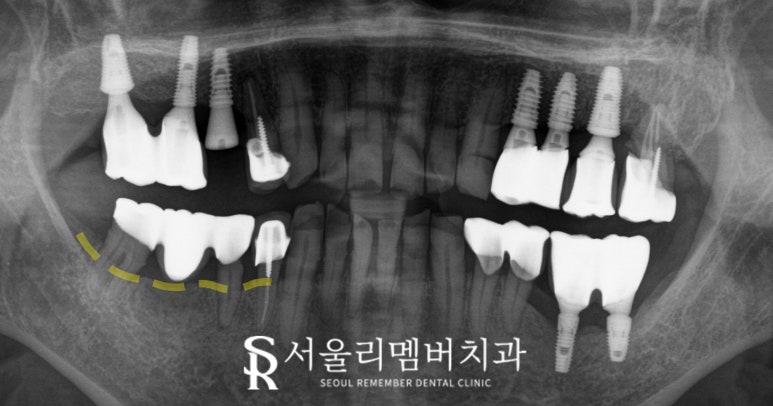

서울대입구역 치과 에서는 엑스레이 검사를 통해

환자의 구강 상태를 다음과 같이 확인했습니다.

#45, #47 치은 퇴축 및 마진 드러남

기존 bridge 부위는 치은 퇴축으로 인해

마진이 보여지게되어 재수복이 필요했습니다.

치은 퇴축은 그대로 방치 시

통증과 그 사이로 세균이 침투해

우식이 생길 수 있습니다.

전치부 치경부 마모 심화

앞니 중 일부 치경부쪽이 마모되어

신경 가까이까지 손상되었고,

이는 추가 신경 치료가 필요한 상태였습니다.

이는 치아 뿌리 부분이 닳아 발생하는 것으로,

방치한다면 이가 부러질 위험이 있어

조속한 처치가 필요합니다.

하악 어금니 45와 47 치아는 상태가 좋지 않아

발치 후 46과 47 부위에 임플란트를

식립하여 이를 대체했습니다.

45의 치조골이 불안정하기 때문에

무리한 식립은 진행하지 않고

46,47과 함께 연결하는 캔틸레버 방식으로

브릿지를 제작하여 교합 기능과

심미성을 모두 회복시켰습니다.